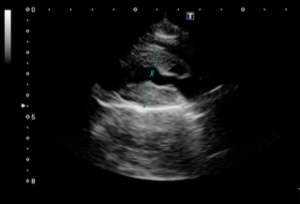

心臓の中では血液は一方通行で流れています。そのために心臓内には逆流を防ぐ弁が付いています。逆流を防ぐ弁の1つである僧帽弁の異常により、血液の逆流を生じる疾患です。その原因として僧帽弁の粘液腫様変性がもっとも多いですが、その他に感染性心内膜炎、機能性僧帽弁逆流などが原因となります。血液の逆流が少ないと症状は現れませんが、心臓の聴診で心雑音が聴かれます。逆流量が多くなると、元気がない、疲れやすい、寝ている時間が増えるなどの症状がみられてきます。